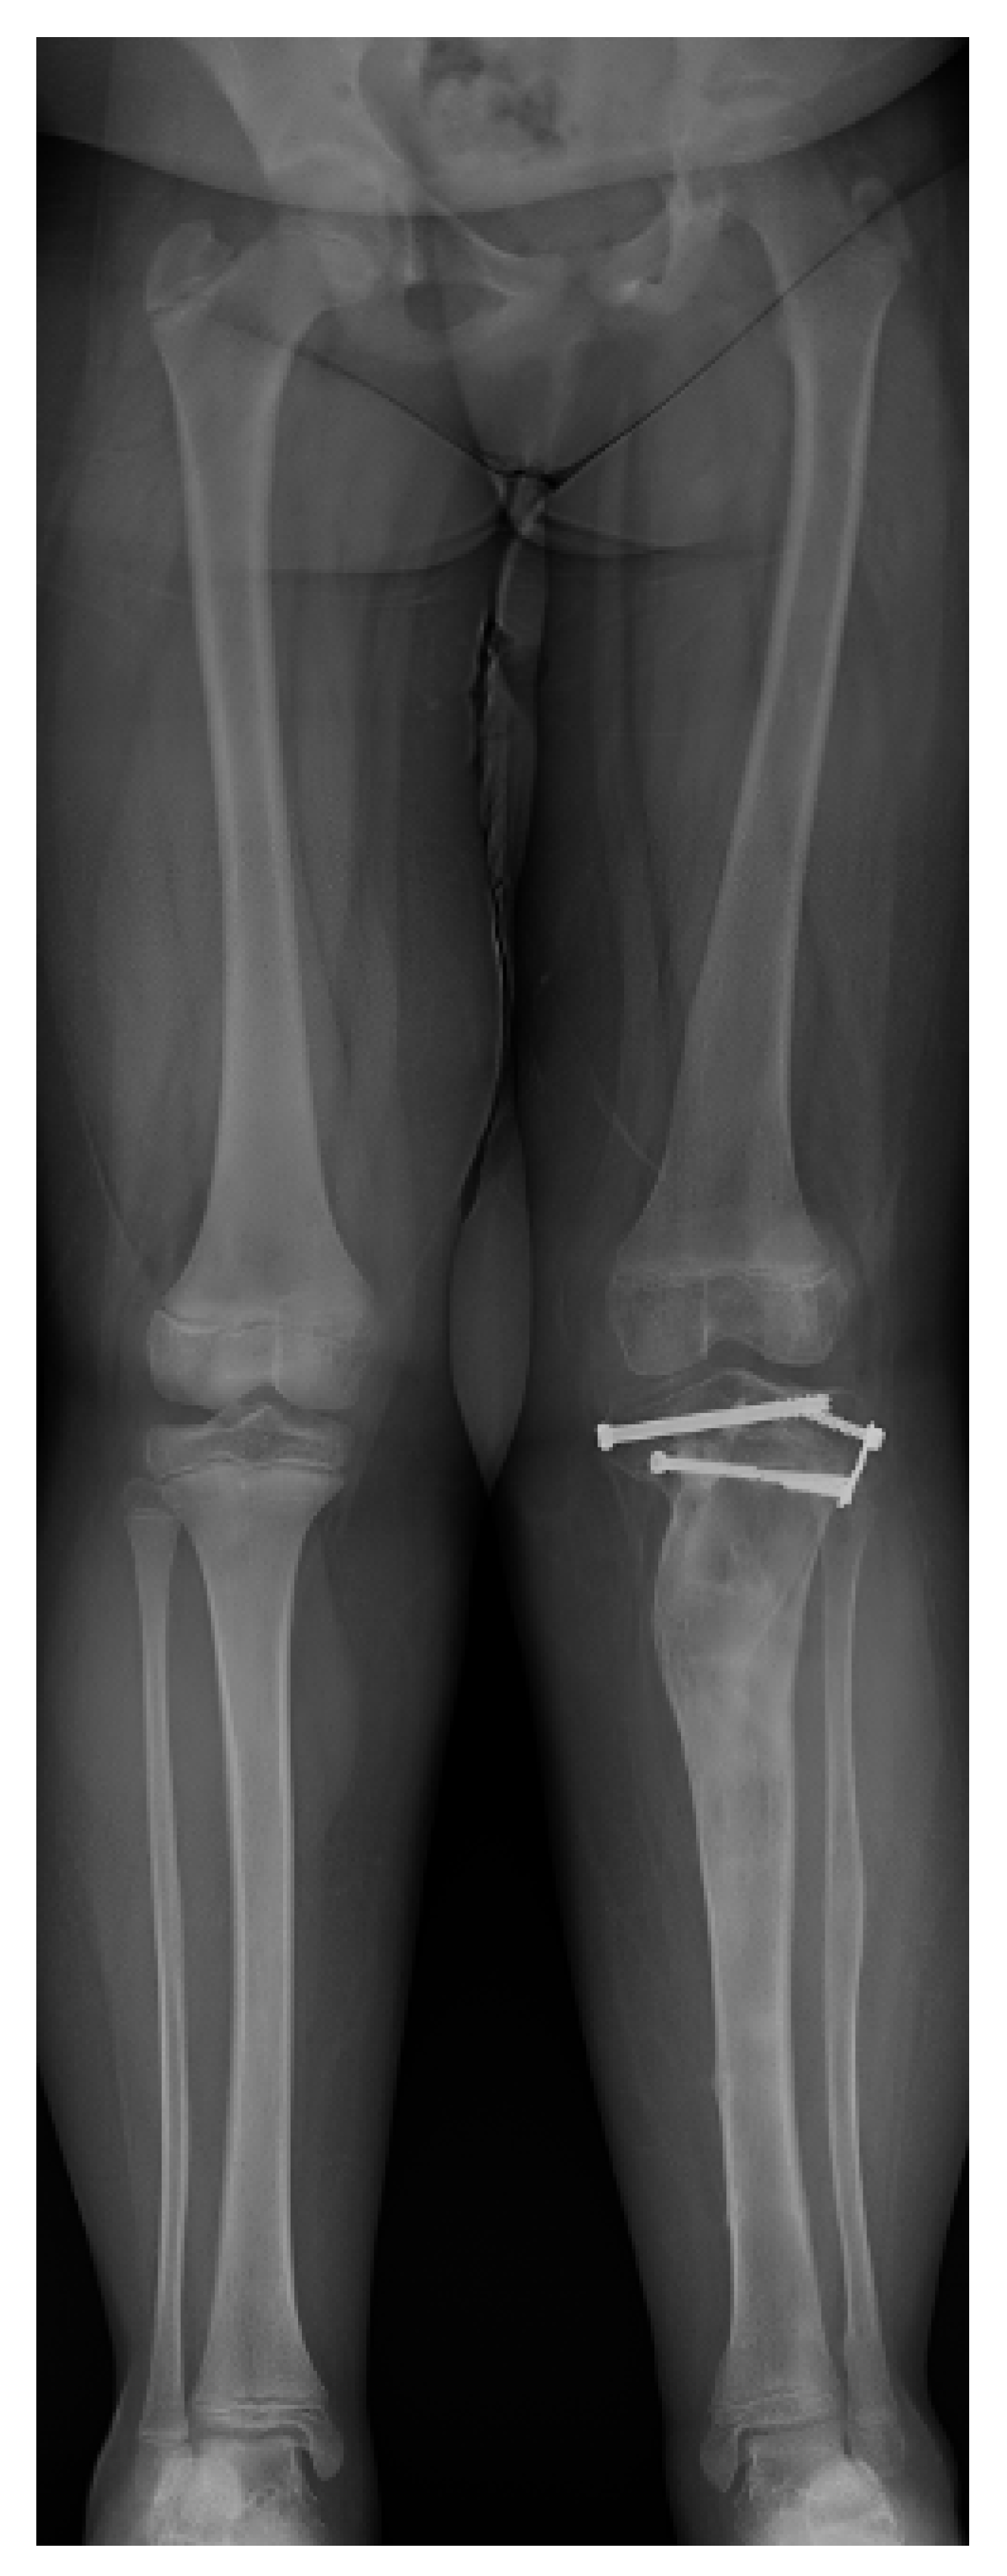

17. Gradual Correction with External Fixation

18. Late-Onset Tibia Vara (LOTV)